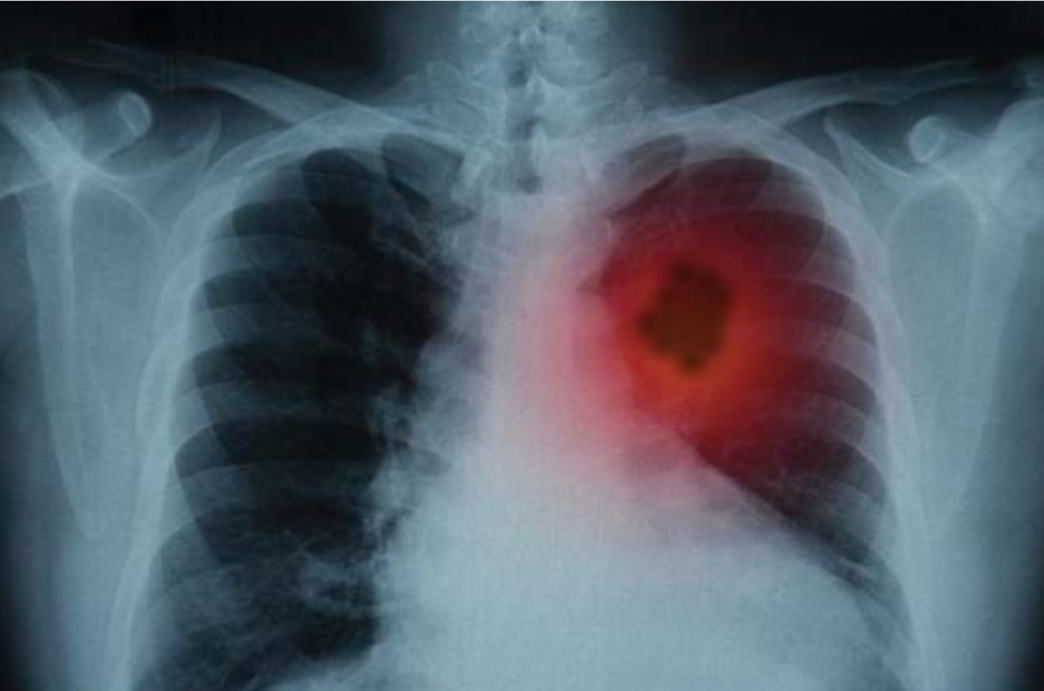

Sëfundmi, shkencetarët kanë zbuluar një përllogaritës mbi mundësine e prekjes nga kenceri i mushkrive përgjatë 6 apo 16 viteve të ardhshme duke marrë në konsideratë si vlerësues kryesor duhanpirjen dhe peshën.

Testet kanë treguar se përllogaritësi në fjalë është 90 për qind i saktë nëse të dhënat i jepni korrekte.

Albeu.com ju këshillon të bëni një verifikim të gjendjes suaj përmes këtij përllogaritësi, megjithatë është mjeku ai që bën vlerësimin final tuajin.